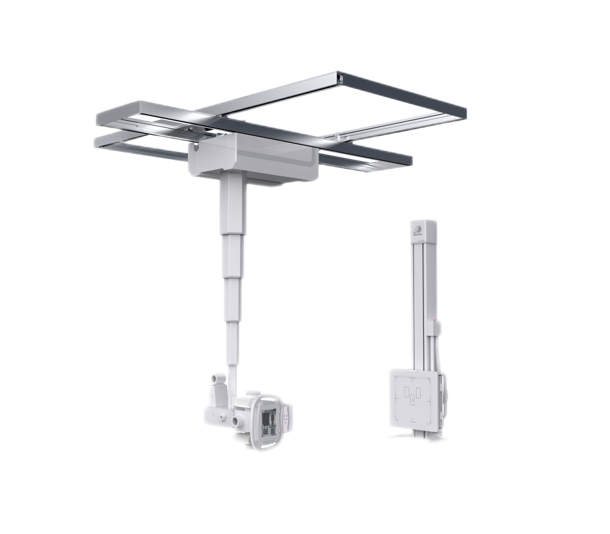

集靜態DR攝影與動態的透視、造影功能于一身,可進行頭部、胸部、腹部和四肢等部位的DR靜態攝影、各種動態及造影檢查,還能在可視的情況下完成高清DR點片,有效避免傳統靜態DR盲拍造成的漏診和誤診,滿足多種臨床診斷需求。

搭載17x17英寸動態平板探測器,動態幀率高達30幀/秒,突破傳統盲拍局限,通過動態實時連續成像,對于重疊部位、易被遮擋的病灶進行多角度動態觀察,瞬時實現高清點片,提升篩查診斷的精準性。

● 雙向自動跟蹤

探測器與球管雙向自動跟蹤,無需手動校正,多角度高精度實時同步;

胸片位、床上位電動轉換,一鍵到位。

● 手動電動一體化

懸吊配備手動模式與電動模式,沿天軌橫縱移動時可選手動或電動,滿足不同醫護人員使用習慣。